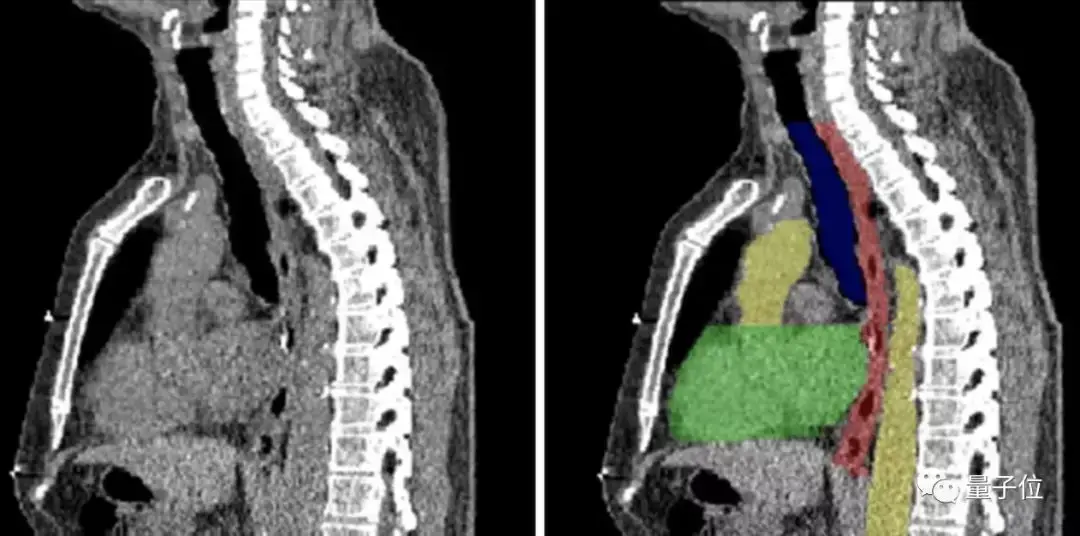

图像分割,顾名思义,就是将图像切分为多个区域,来简化或改变图像的表现形式,从而让图像变得更加容易解读和分析。

目前,图像分割技术用在了肿瘤和其他病理位置定位、组织体积测量、解剖学研究、计算机辅助手术、治疗方案制定以及临床辅助诊断等多个细分领域。

图像分割的实现方式也不难理解——以图像中的自然边界,例如物体轮廓、线条等,将图像切分为多个区域。

在计算机中,是对图像中的每个像素加上标签,并认为具有相同标签的像素有着某种共同视觉特性,从而来实现分割。

传统中有基于聚类、阈值、边缘、区域等特征的方法。但随着AI技术的发展,基于深度学习的方法效果出众,超过人类,成为最广泛的应用。

这其中,全卷积网络(Fully Convolutional Network, FCN)、U-net 和 V-net 是常见的几种基于深度学习的图像分割方法。

但在医疗领域中,应用最为广泛的则是U-net 。需要分割的图像有其独特性,大多数情况下是针对一个指定器官的成像,而非全身。

器官本身结构比较固定,语义信息并非特别丰富。

所以高级语义信息和低层级特征就显得重要,而 U-net 的 U 型结构和跳跃连接在这种场景中,可以发挥出更大作用。

近年来,U-net 在医学影像 分割领域良好的应用效果,已在很多部署中得到充分了证明。

良好的图像分割模型,能有效帮助医疗机构提高医学影像判读效率,进而增强临床诊疗能力、提升疾病治愈率以及减少病患等待时间,弥补因医疗机构影像科资源缺乏带来的多种问题。

但医疗领域的图像分割对时效性要求更高。

通常情况下,留给病患的黄金诊疗窗口往往只有数十分钟。因此,如果图像分割 AI 应用的推理效率不够高,就有可能延误宝贵的抢救时间。

这就决定想要将图像分割应用到真正的医疗场景中,一方面需要基于不同的图像分割类型对模型进行优化,另外一方面则需要强大稳定的计算能力来完成推理。

怎么进一步落地?英特尔提供了工具,比如OpenVINOTM工具套件以及至强处理器系列产品等等, 能够在在保证 U-net 模型高准确率的同时,推理时间大幅降低85%。

在报告中不仅给出了具体的使用方法,也放出了不少已经落地的案例,比如东软的eStroke溶栓取栓影像平台,西门子的心腔检测和量化模型等等。